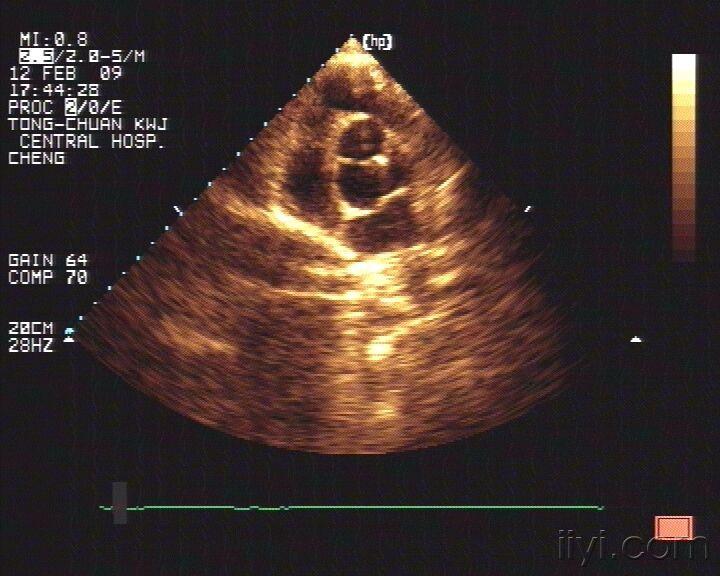

主动脉左右冠瓣交界处钙化并关闭不全

图片尺寸720x576